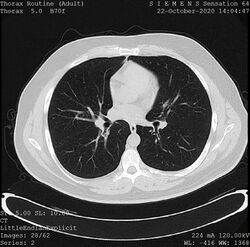

• X-ray computed tomography (CT), or Computed Axial Tomography (CAT) scan, is a helical tomography technique (latest generation), which traditionally produces a 2D image of the structures in a thin section of the body. In CT, a beam of X-rays spins around an object being examined and is picked up by sensitive radiation detectors after having penetrated the object from multiple angles. A computer then analyses the information received from the scanner's detectors and constructs a detailed image of the object and its contents using the mathematical principles laid out in the Radon transform. It has a greater ionizing radiation dose burden than projection radiography; repeated scans must be limited to avoid health effects. CT is based on the same principles as X-Ray projections but in this case, the patient is enclosed in a surrounding ring of detectors assigned with 500–1000 scintillation detectors[13] (fourth-generation X-Ray CT scanner geometry). Previously in older generation scanners, the X-Ray beam was paired by a translating source and detector. Computed tomography has almost completely replaced focal plane tomography in X-ray tomography imaging.